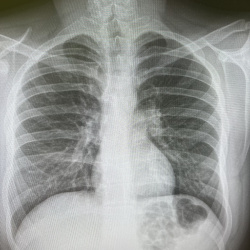

20.02.2025 - 09:19

Пацента 57 лет жалобы на кашель, температуру до 38 градусов. Из анамнеза : ВИЧ инфицирована.